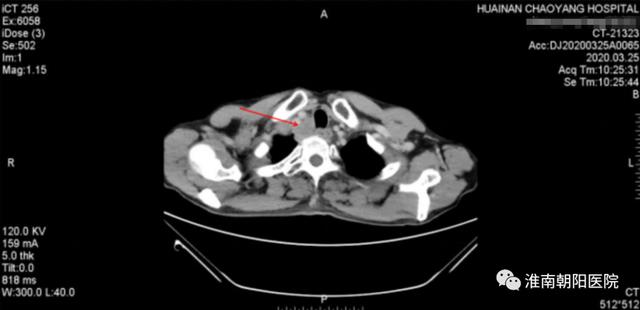

患者张大爷是一位来自寿县寿春镇的淳朴农民,2019 年 6 月初的一天,他吃饭时感觉明显梗噎疼痛感,症状越来越重。2019 年 8 月初去医院检查,通过胸部 CT 及胃镜等检查确诊为:「食管中上段鳞状细胞癌」。

(上图红色箭头就是食管肿瘤)